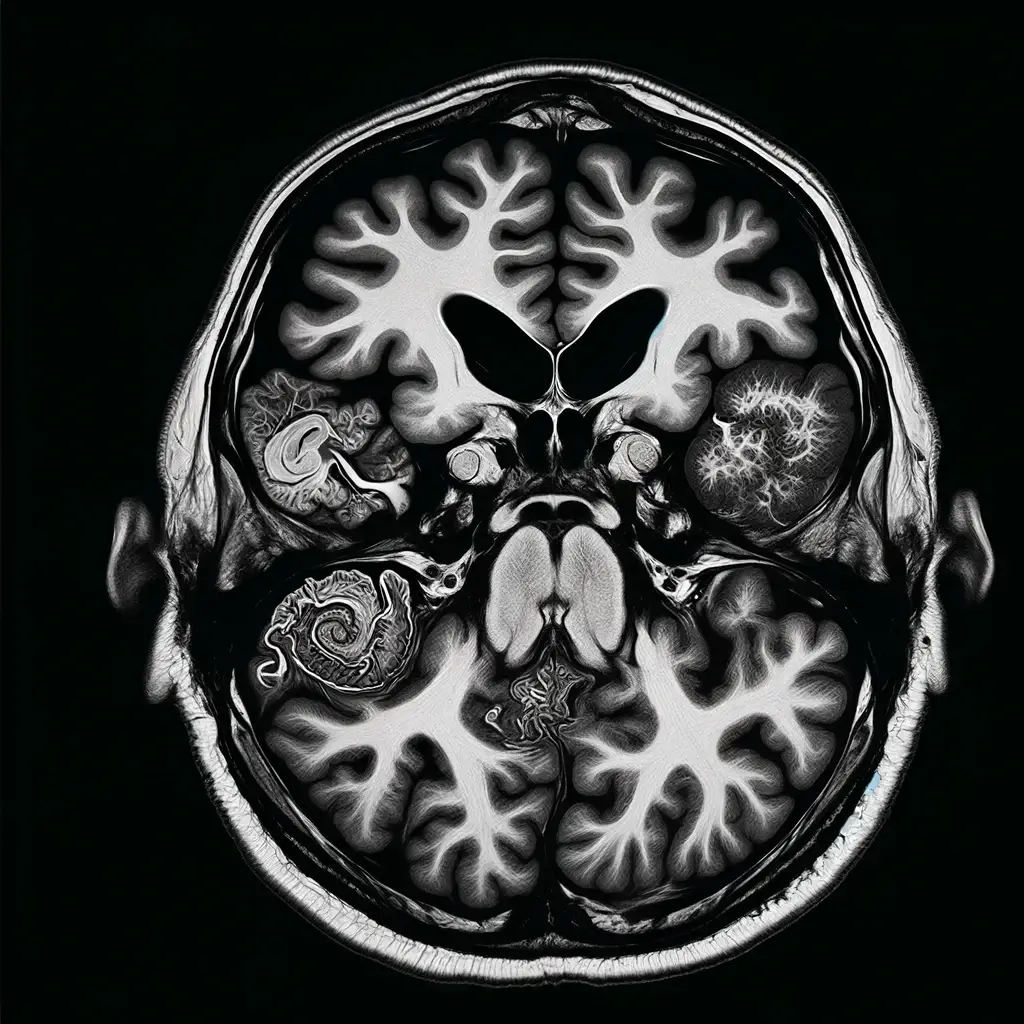

주요 특징으로는 제4뇌실의 확장 및 소뇌 발달 부전이 있으며, 제4뇌실의 출구가 부분적 또는 완전히 막혀 있어 뇌척수액의 흐름이 차단되고, 이로 인해 제4뇌실이 확장됩니다. 이러한 소뇌의 발달 부전은 운동 능력의 결핍으로 이어집니다.

- 자기공명영상(MRI) 촬영 : 강력한 자기장을 이용해 몸의 내부 구조를 상세하게 보여주며, 엑스레이를 사용하지 않습니다.